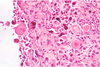

Cataract

The most common disease of the lens

Swelling/degeneration of lenticular fibersopacity

Lens response to injury:

Hydropic swelling of injured fibersfiber fragmentation & disintegration

Hyperplasia and fibrous metaplasia of lens epithelium

Posterior lens epithelial migration

When chronic (“hypermature”): shrinking and wrinkling of lens capsule and mineralization

What causes a cataract?

Radiation

Increased IOP (Glaucoma)

Endophthalmitis

Hereditary defect in lenticular metabolism

Diabetes mellitus (high glucose in aqueous)

Trauma

ANYTHING THAT DAMAGES THE LENTICULAR FIBERS!